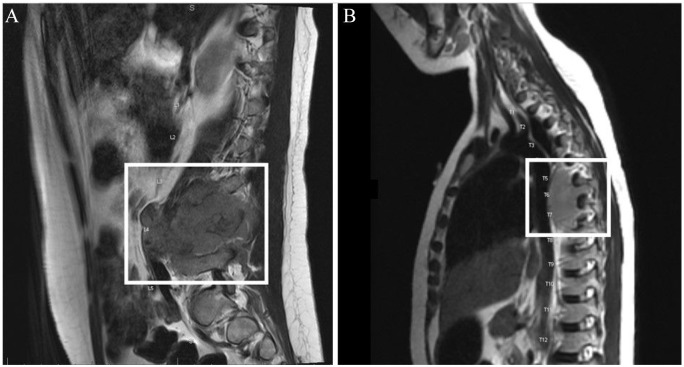

泌尿系统症状是儿科女性急诊中最常见的原因之一,可能与多种疾病有关,如感染(最常见)、性创伤和罕见的肿瘤过程。在此,我们报告了一例 7 岁女性的病例,她因泌尿系统症状和阴道疼痛多次急诊就诊,并接受了抗生素和抗真菌药物的经验性治疗,但症状未见好转。在此期间,她的血液化验和体格检查均未发现异常。在第三次急诊就诊时,她被转到我院接受进一步评估。影像学检查发现,她的椎体在L4和T6水平有膨胀性病变,并伴有压迫性脊髓病变,下肢有多处骨和软组织病变。患者出现鞍区麻醉,需要紧急减压并对硬膜外肿块进行活检,最终病理结果为 B 淋巴细胞白血病/淋巴瘤。B-ALL/B-LBL是最常见的小儿血液系统恶性肿瘤,通常表现为发热、肝脾肿大、淋巴结肿大、骨痛和出血。偶尔也有非典型表现,如骨和关节疼痛、骨质疏松症、椎旁可触及肿块等。然而,这是首例描述这种疾病非常不寻常和陌生表现的病例报告,给诊断带来了很大困难,导致治疗延误。本病例报告提醒人们,对普通治疗无效的儿童患者出现异常疼痛或任何非特异性表现时,应格外谨慎,以免错过这一肿瘤过程。

Urinary symptoms are one of the most common reasons for emergency visits in females of pediatric age group and can be associated with various conditions like infections (most common), sexual trauma and rarely neoplastic processes. Here, we report a case of a 7-year-old female who presented in the emergency multiple times with the complaints of urinary symptoms and vaginal pain and was empirically treated with antibiotics and antifungals without symptomatic improvement. Her blood tests, physical examination during this time remained unrevealing. She was then transferred to our institution on her third emergency visit for further evaluation. On imaging studies, she was noted to have expansile lesions on her vertebral body at the L4 and T6 levels with compressive myelopathy with multiple bone and soft tissue lesions throughout her lower extremities. Patient developed saddle anesthesia requiring emergent decompression and biopsy of the epidural mass with the final pathology coming back as B-lymphoblastic leukemia/lymphoma. B-ALL/B-LBL is the most common pediatric hematologic malignancy and usually presents with fever, hepatosplenomegaly, lymphadenopathy, bone pain and bleeding. Occasionally, atypical presentations like bone and joint pain, osteoporosis, palpable paravertebral mass have been described. However, this is the first case report to describe a very unusual and unfamiliar presentation of this disease causing significant diagnostic difficulty resulting in delayed treatment. This case report can aid as a reminder that unusual pain or any nonspecific manifestations in pediatric patients, refractory to common treatment should be investigated with extreme diligence not to miss this neoplastic process.